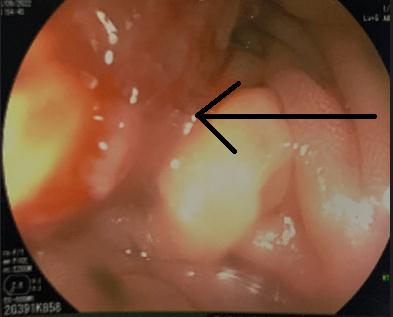

Cắt lớp vi tính ổ bụng: Các quai ruột non và khung đại tràng giãn lớn, đường kính lớn nhất 57mm, trong có mức dịch khí, vị trí chuyển tiếp là đoạn đại tràng trái, tại vị trí này, thành đại tràng dày nhẹ.

![]() |

Hình 1. Hình ảnh cắt lớp vi tính ổ bụng